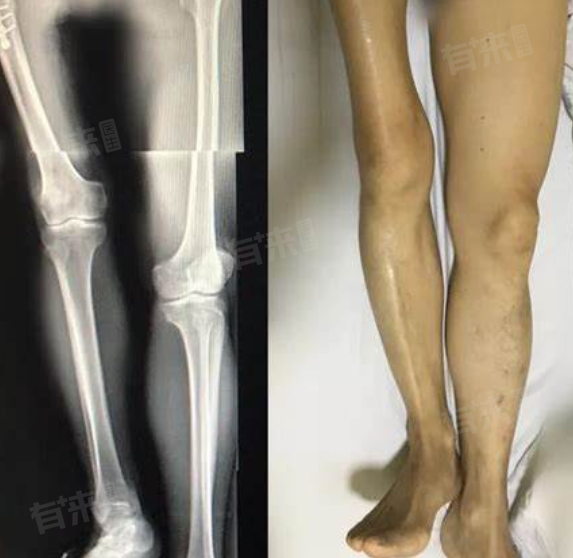

3、X线检查:X线能够对腿部骨骼进行整体成像,医生通过观察骨骼的结构和形态,有助于发现骨折、骨肿瘤等骨骼病变,评估其与腿粗差异之间的关联。